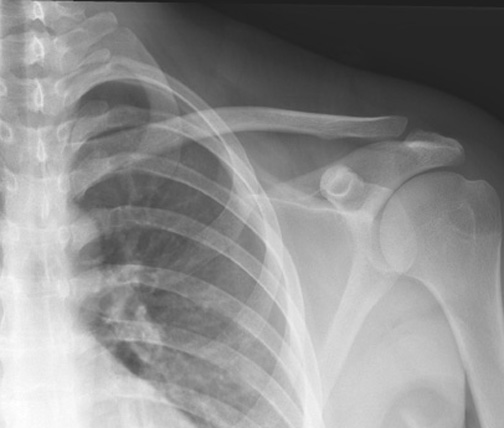

Identify parts of the clavicle. Click the image for labeling.